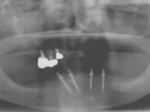

術前術前骨の高さが不足している場合、通常のインプラントでは処置が不可能なものが多い。特殊なショートインプラントを用いて可能になる例。 術前 術前CT像術前CT像術前CT像、下歯槽神経が下あごの中央部を走行しているため利用できる骨の高さが少ない。 埋入予定計画埋入予定計画埋入予定計画 術後レントゲン術後レントゲン、ひだりは少し神経をおそれすぎてやや埋入深度が不足、しかしこれでもしっかりと骨と固着した。

上部装着後のレントゲン像上部装着後のレントゲン像上部装着後のレントゲン像 術前口腔内写真術前口腔内写真術前口腔内写真 術後口腔内写真術後口腔内写真術後口腔内写真、食事がおいしくなったと非常に満足されている。